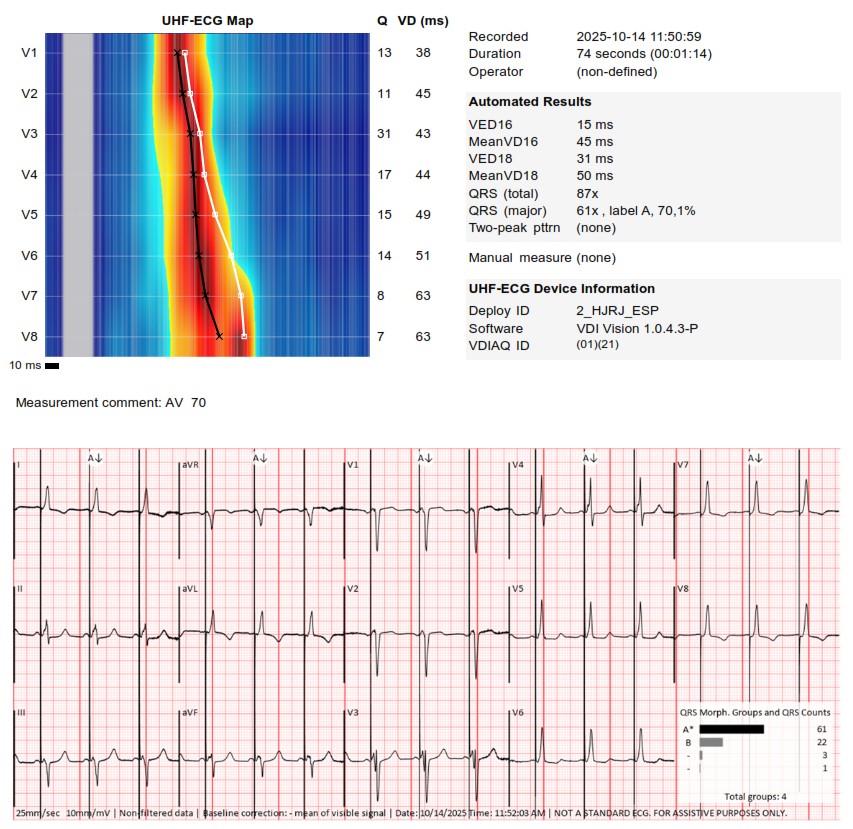

I strongly support HBP, but in this case,the great improvement in QRS didn't correct the asynchrony measured with UHF ECG.We opted for LBBAP despite the RV delay.The final programming AV 70 ms and fusion with native rhythm achieved the best result with UHF ECG(very useful tool)

Challenging LOT CRT case. Final UHF ECG recordings very satisfactory @curilakarol @MirekNavratil1 #Epeeps